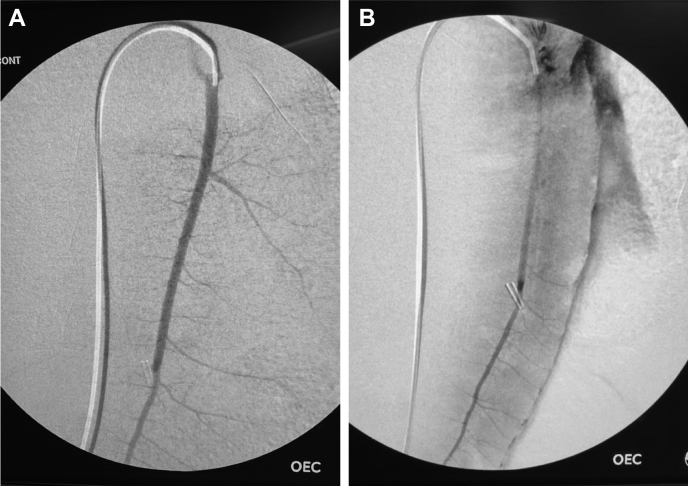

After completion of controlled hemorrhage, a flexible, angled, hydrophilic 0.035″ guidewire (Glidewire; Terumo, Elkton, Md) and a 4F angled hydrophilic catheter (Glidecath; Terumo) were used to select the splenic artery under fluoroscopic guidance (OEC 9900 Elite; GE, Chicago, Ill). Baseline digital subtraction angiography of the spleen was performed using a hand injection of contrast, and a flexible wire was left in the splenic artery while the catheter was withdrawn into the aorta to permit free antegrade splenic flow (Fig 3).

Fig 3.

Representative angiograms illustrating pretransection (A) and post-transection (B) appearance. Note extravasation along the splenic border and loss of arboreal appearance after transection. Reprinted with permission from original publication.6

Splenic injury and embolization

After marking of the longitudinal midline of the spleen, the organ sharply and completely transected 1 cm lateral to the midline, as described by Sondeen et al11 (Fig 2). Free splenic hemorrhage was allowed for 5 minutes; then the catheter was advanced into the proximal splenic artery over the wire for angiography and treatment (Fig 3). Shed blood from the splenic injury was continuously suctioned and measured. In control animals (n = 3 noncoagulopathic, n = 3 coagulopathic), no treatment was performed. In the treatment groups (n = 5 each), one of three endovascular embolization treatments was performed through the catheter. Smaller control groups were used to minimize the use of animals while ensuring a predictable response to hemorrhage and coagulopathy given previous experimental experience.6

Immediate post-treatment angiograms in all treatment groups revealed complete cessation of flow within the splenic artery and no extravasation (Fig 8). Similar results were observed when analyzing postembolization treatment blood loss. In noncoagulopathic conditions, all three treatments resulted in significantly reduced splenic bleeding than was seen in the control group. With coagulopathy, however, only hydrogel treatment produced a significant reduction in bleeding over controls. No significant intergroup differences were observed between individual treatments (Fig 9).